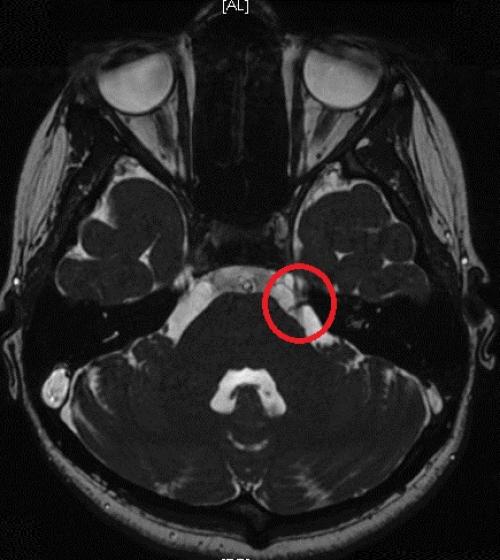

![]() | ![]() | ![]() |

| Выход пломбировочного материала за верхушку зуба вызывал жестокие боли во второй ветви тройничного нерва у мужчины. Вид сбоку:

зуба, кружком обведен | Стреляющая боль во всех трех ветвях была следствием плохого кровообращения в мозговых отделах тройничного нерва у пожилой женщины. Кружком обведен участок мозга, пострадавший от закупорки одного из сосудов головного мозга. Проверить сосуды головы и шеи | Невралгия тройничного нерва была у молодой женщины из-за давления одной из мозговых артерий на корешок тройничного нерва. На МР-томограмме видно пересечение тройничного нерва (идет вертикально) с артерией (идет горизонтально). Артерия оказывала давление на тройничный нерв в месте его выхода из ствола мозга. |